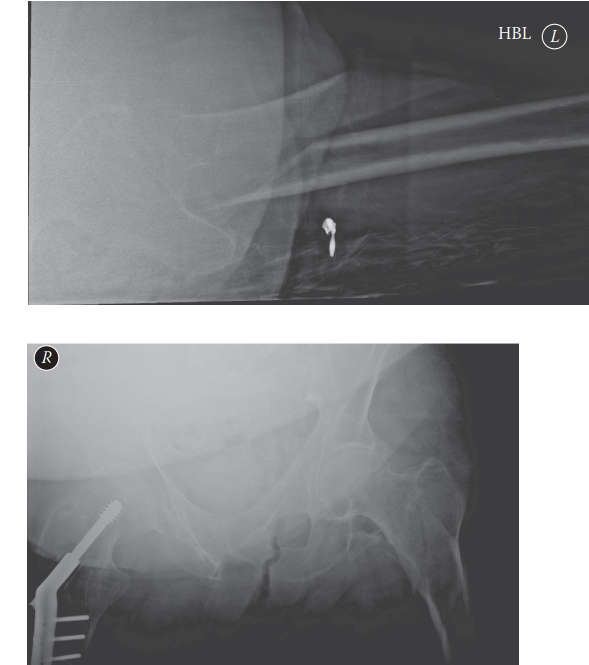

Can you describe the radiographs? These are AP and lateral radiographs of the left hip. The subtrochanteric r…